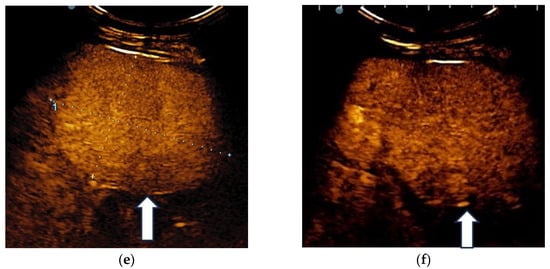

3.4. Real-Time Tissue Elastography

| Elasticity Type | Color Code |

|---|---|

| Type “a” | Homogenously green |

| Type “b” | Mosaic pattern with dominant green areas |

| Type “c” | Mosaic pattern with dominant blue areas |

| Type “d” | Homogenously light blue |

| Type “e” | Homogenously dark blue |

| RTE | Liver Adenoma | HMG | FNH | Complicated Liver Cyst | HCC | iCCA | Liver Metastases | Liver Lymphoma |

|---|---|---|---|---|---|---|---|---|

| Type “a” | 3 | 1 | ||||||

| Type “b” | 1 | 1 | 10 | 3 | 1 | |||

| Type “c” | 1 | 24 | 3 | 6 | ||||

| Type “d” | 1 | |||||||

| Type “e” | 5 | 3 | 1 |